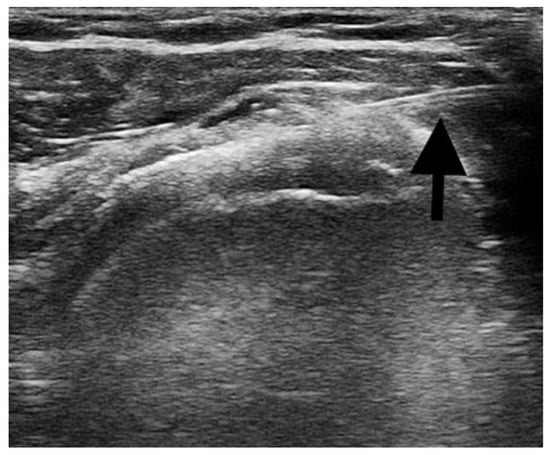

- Ultrasound-guided injections: the procedures were performed with the patient supine and positioned with the shoulder adducted and slightly extra rotated, the upper limb laying along the side. A US machine (Mindray® M7 Bio-Medical Electronics Co, Ltd., Shenzhen, China) with a linear transducer (8–12 MHz) was used to identify the subacromial bursa and to guide the injection procedure. After the preparation of the sterile field, a US-guided percutaneous injection of 1 mL of 40 mg triamcinolone acetonide combined with 3 mL of 1% lidocaine was performed in the affected subacromial bursa [31,32]. A 22-gauge needle was used and the correct positioning of the needle directly into the bursa was real-time confirmed under US guidance. Figure 1 shows the US image of the percutaneous injection procedure.